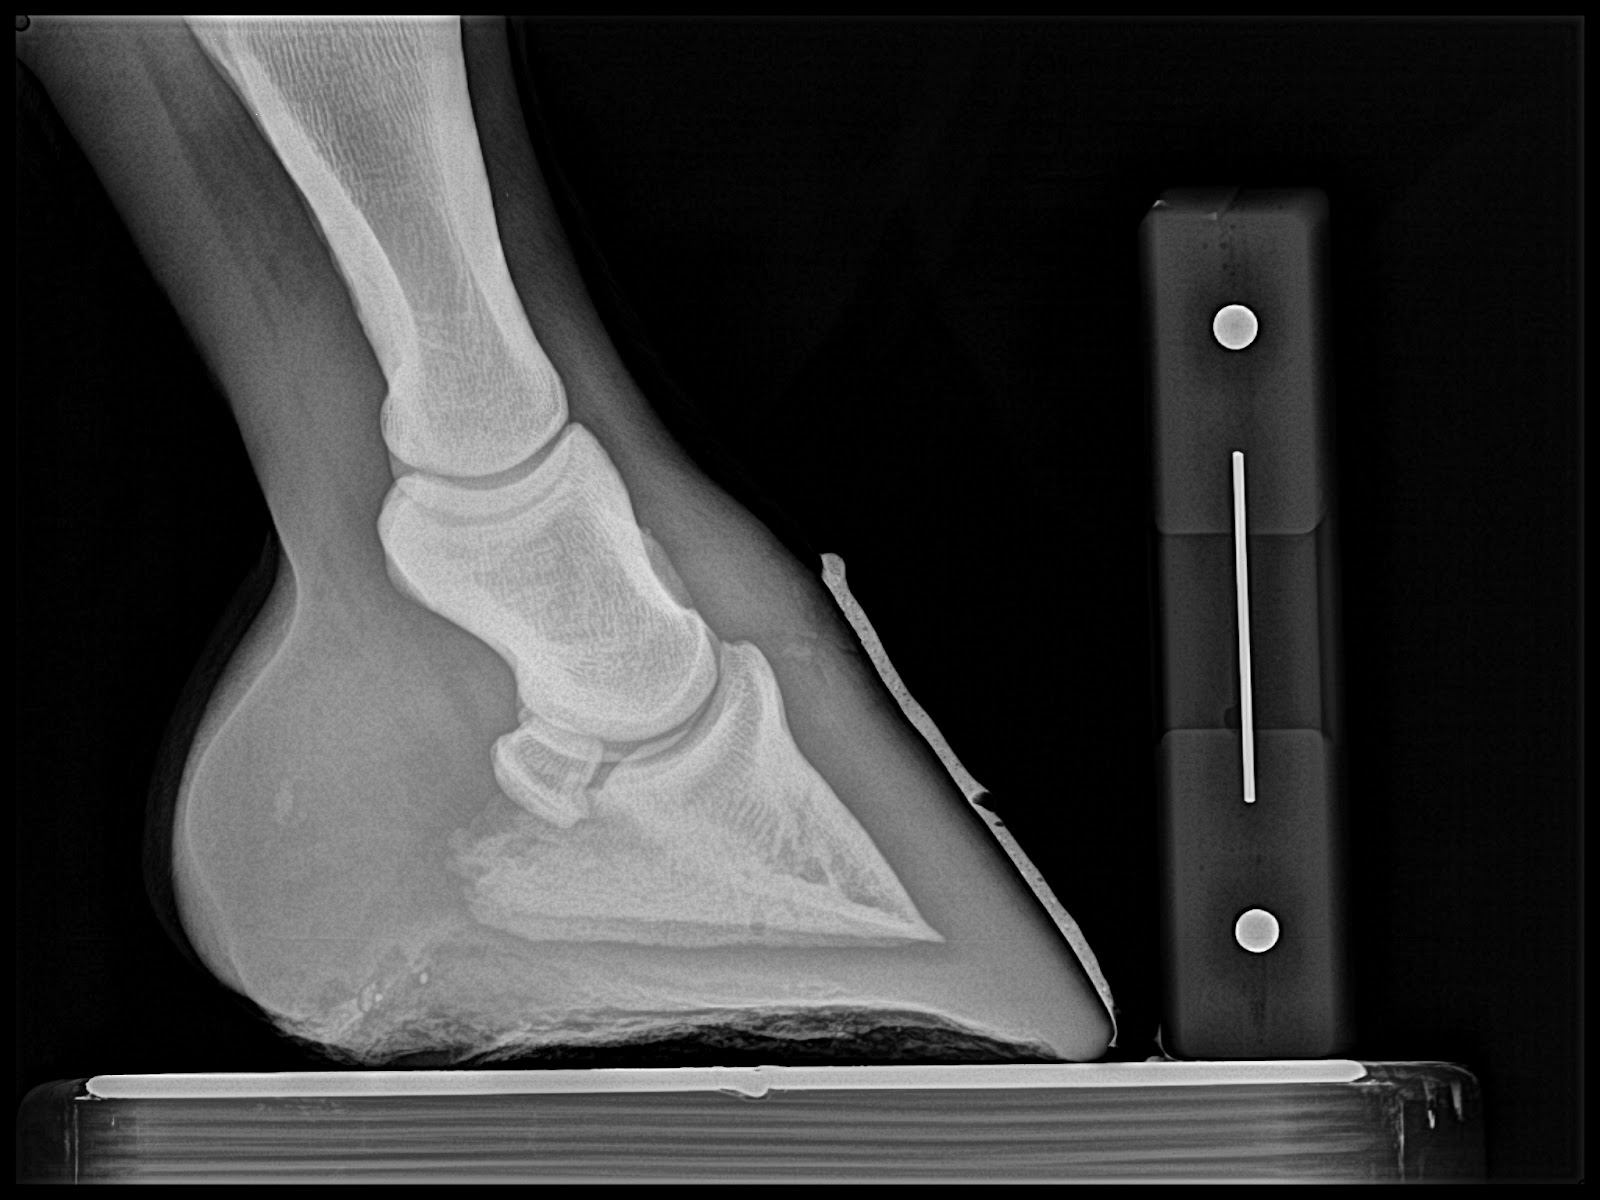

Next Case: Older teenage trail and lesson horse. He has been plagued with Navicular disease and is 2/5 lame on left front. Immediate improvement is noted and absolutely no head bobbing at next reset. The first three images are from the day of the clinic and the last two are pre shoeing radiographs from the reset. I misplaced the day of the clinic rads for this case.

| This is is post trim with application of barium paste to accentuate the trim performed by Dr. Redden. |